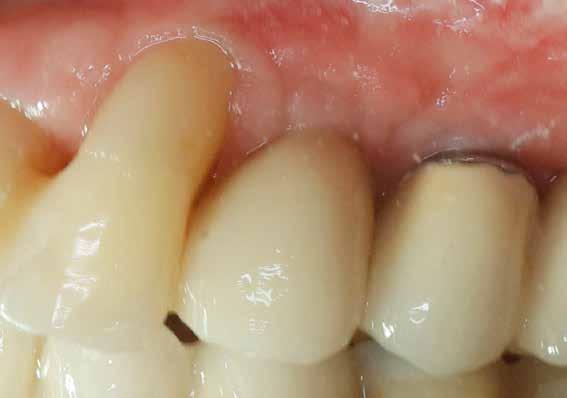

A 2020 januárjában elkezdett kezeléssorozat befejezését az év márciusában, hazánkba is begyűrűző Covid-19 pandémia késleltette, így kb. 6 hónap gyógyulás után láttunk hozzá az emergencia profil és a gingivális zenit ideiglenes koronával történő formázásához (11. és 12. kép). A 3 hetente végzett apró alakításokkal sikerült megfelelő ínyprofilt kialakítani, a „rózsaszín esztétika” a páciens számára is megfelelő volt. A bal felső nagymetsző fog meziális kompozit tömés cseréjét követően, individualizált nyitott kanalas lenyomati fejet készítettünk: az akrilát ideiglenes korona profilját átlátszó szilikonnal lemásoltuk, majd a körszimmetrikus gyári lenyomati fej és az ideiglenes korona kontúrja közötti hézagot folyékony kompozittal töltöttük ki (13. kép). Az így készített egyéni lenyomati fejjel vettünk lenyomatot a végleges, kerámialeplezésű cirkónium-dioxid vázas, átmenő csavaros rögzítésű koronához. (A fogtechnikai munkát Nébl Péter fogtechnikusmester készítette.), (14., 15., 16 és 17. képek).

A kész korona átadásakor a páciens elégedett volt az esztétikával, az azóta eltelt évben rendszeres kontrollokon jelent meg, melyek során meggyőződtünk a kemény- és lágyszövetek stabilitásáról (18. és 19. képek).